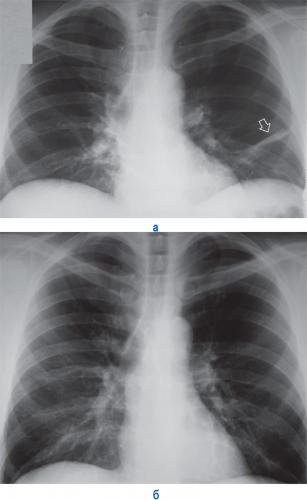

На рентгеновских снимках выявляют следующие признаки, указывающие на спадение легочной ткани:

Однородное затемнение в области поражения. Размеры тени зависят от вида ателектаза: при долевом выявляется обширное затемнение, при сегментарном — в виде клина или треугольника, расположенного вершиной к корню легкого, дольковые ателектазы множественные и похожи на очаговую пневмонию. Дистензионный ателектаз расположен низко, около диафрагмы, имеет небольшие размеры и вид поперечных полос или темных дисков. Смещение органов: при компрессионном ателектазе смещение наблюдается в здоровую сторону, так как на стороне поражения давление больше, при обтурационном, наоборот – смещение будет в сторону ателектаза, так как на стороне поражения нарастает притягивающее отрицательное давление. Подъем купола диафрагмы – это видно по расположению печени.

Помимо всего перечисленного выше, рентгеноскопия, то есть исследование «вживую», позволяет увидеть куда смещаются органы в зависимости от фазы дыхания, кашля. Это является дополнительным признаком ателектаза, помогающим выявить тип болезни.

Предварительным, рентгенологическим диагнозом является «синдром правой доли», при котором выявляется затемнение площади средней доли правого легкого.

Частое возникновение ателектаза правого легкого связано с анатомическими особенностями правого среднедолевого бронха: он узкий и длинный, поэтому часто происходит его перекрытие при патологическом процессе.